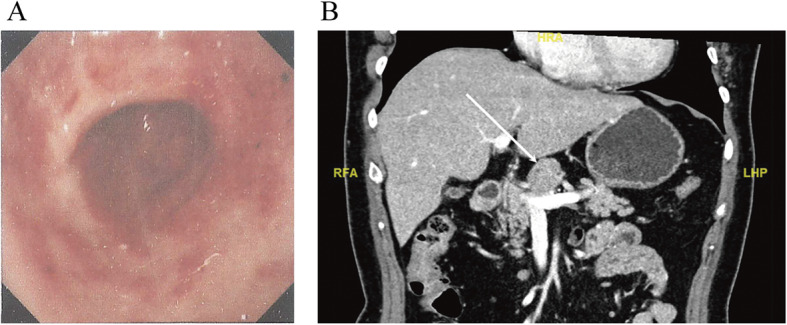

A 61-year-old woman complained of epigastric discomfort for several years. She received gastroscopy that indicated a slight superficial mucosal erosion of the gastric antrum with negative Helicobacter pylori (Fig. 1a), and ultrasonography found an upper abdominal mass. Contrast-enhanced abdominal computed tomography (CECT) revealed the existence of a solitary nodule above the neck of the pancreas—size 29 mm × 27 mm, clear boundary, uniform density, lobulated, and slowly reinforced with contrast (Fig. 1b). The radiological findings diagnosed the lesion as benign. The patient’s discomfort improved when she took omeprazole for 2 weeks and chose to wait and see instead of undergoing biopsy or operation. A repeat CECT scan was done 3 months later, which showed a slight increase in the size of the solitary nodule (32 mm × 25 mm), with no other abnormal findings (Fig. 2a). The patient had no fever and no loss of weight. Body examination did not reveal any abnormal signs, and no enlarged superficial lymph node was detected. Laboratory analysis showed a slightly increased blood glucose and triglyceride. Tumor biomarkers (carcinoembryonic antigen (CEA), carbohydrate antigen (CA) 19-9, CA 125, and CA 242) and immunological tests (β2 microglobulin, immunoglobulin G4, interleukin-2, interleukin-4, interleukin-6, interleukin-10, interferon-γ, and lymphocyte subsets) were all within the normal range.

Fig. 1.

The first preoperative tests. a The first gastroscopy that was taken at another hospital (scanned version of printed report). Slight superficial mucosal erosion of the gastric antrum. b The contrast-enhanced abdominal CT. A solitary nodule above the neck of the pancreas, size 29 mm × 27 mm, labeled by the white arrow